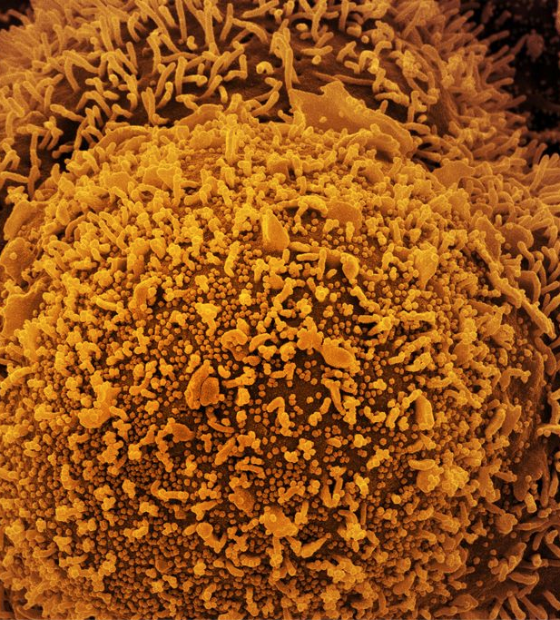

Brasil se aproxima de 6 milhões de casos e 4 mil mortes por dengue

Números são divulgados pelo Ministério da Saúde